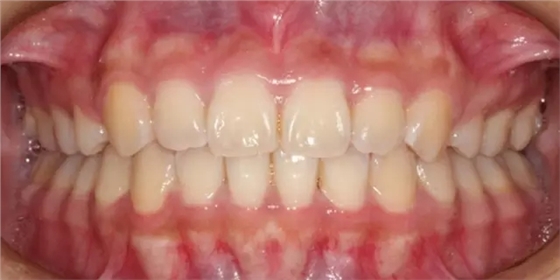

患者側(cè)面凸,鼻唇角較銳,笑時(shí)露齦笑明顯上下牙列擁擠,磨牙尖牙Ⅱ 類關(guān)系,3 度的深覆牙合,上頜中切牙伸長內(nèi)傾拔除上頜雙側(cè)的第一前磨牙,先粘上頜高轉(zhuǎn)矩的自鎖托槽排齊牙列,唇向開展上頜切牙,有一定的覆蓋,粘下頜標(biāo)準(zhǔn)轉(zhuǎn)矩托槽,上頜 1, 2 之間植入種植支抗壓入,同時(shí)后牙 5, 6 之間植入種植支抗內(nèi)收前牙,打開咬合關(guān)閉間隙。治療關(guān)鍵:前牙轉(zhuǎn)矩的控制第 1 個(gè)月 上頜粘上 Damon Q 高轉(zhuǎn)矩托槽,上 .014 熱激活 NiTi 絲。第 3 個(gè)月 上換 .014 x .025 熱激活 NiTi 絲。第 5 個(gè)月 上頜基本排齊,覆蓋增大,上換 .017 x .025 NiTi絲,下頜粘托槽,下 .014 熱激活 NiTi 絲。第 7 個(gè)月 上 .017 x .025 NiTi 絲加搖椅,下?lián)Q .014 x .025 熱激活 NiTi 絲第 9 個(gè)月 上頜換 .019 x .025 NiTi 絲加搖椅,下頜換 .017 x .025 NiTi 絲第 11 個(gè)月 下頜換 .019 x .025 加搖椅,上頜 1, 2 之間, 5, 6 之間植入種植釘,下頜出現(xiàn)散隙。第 13 個(gè)月 上頜換 .019 x .025ss 加搖椅,前牙種植釘用 Power Chain 壓低前牙(每側(cè) 100g),后牙種植釘關(guān)閉間隙(每側(cè) 150g),下?lián)Q .019 x .025ss,Power Chain 關(guān)閉間隙。第 19 個(gè)月 上頜前牙基本壓低到位去除前牙種植釘,繼續(xù)用關(guān)閉間隙,下頜散隙關(guān)閉。

第 22 個(gè)月 上頜覆蓋變小,去除 5, 6 之間種植釘,后牙前移關(guān)閉間隙。第 30 個(gè)月 患者未配合中線牽引,下中線仍有 1mm 右偏,患者對矯治效果滿意要求拆除,拆除固定矯治器,取模制作壓模保持器。 1.骨性 Ⅱ 類的患者內(nèi)收前牙時(shí)需對上頜前牙的轉(zhuǎn)矩進(jìn)行較好的控制才能獲得良好的面型和唇部形態(tài)。 2.露齦笑的患者治療前要分析其病因是唇、牙齦、牙齒、牙槽骨、上頜骨或多種因素結(jié)合,再制定矯治方案。 3.Ⅱ 類第二分類伴露齦笑的患者的上頜前牙移動軌跡是唇向開展-壓低-整體內(nèi)收。 4.Ⅱ 類第二分類牙齒舌傾比較厲害的情況,上頜中切牙慎用樹脂咬合墊。 5.壓低前牙或控根移動時(shí)容易發(fā)生牙根的吸收,需輕力緩慢的移動。